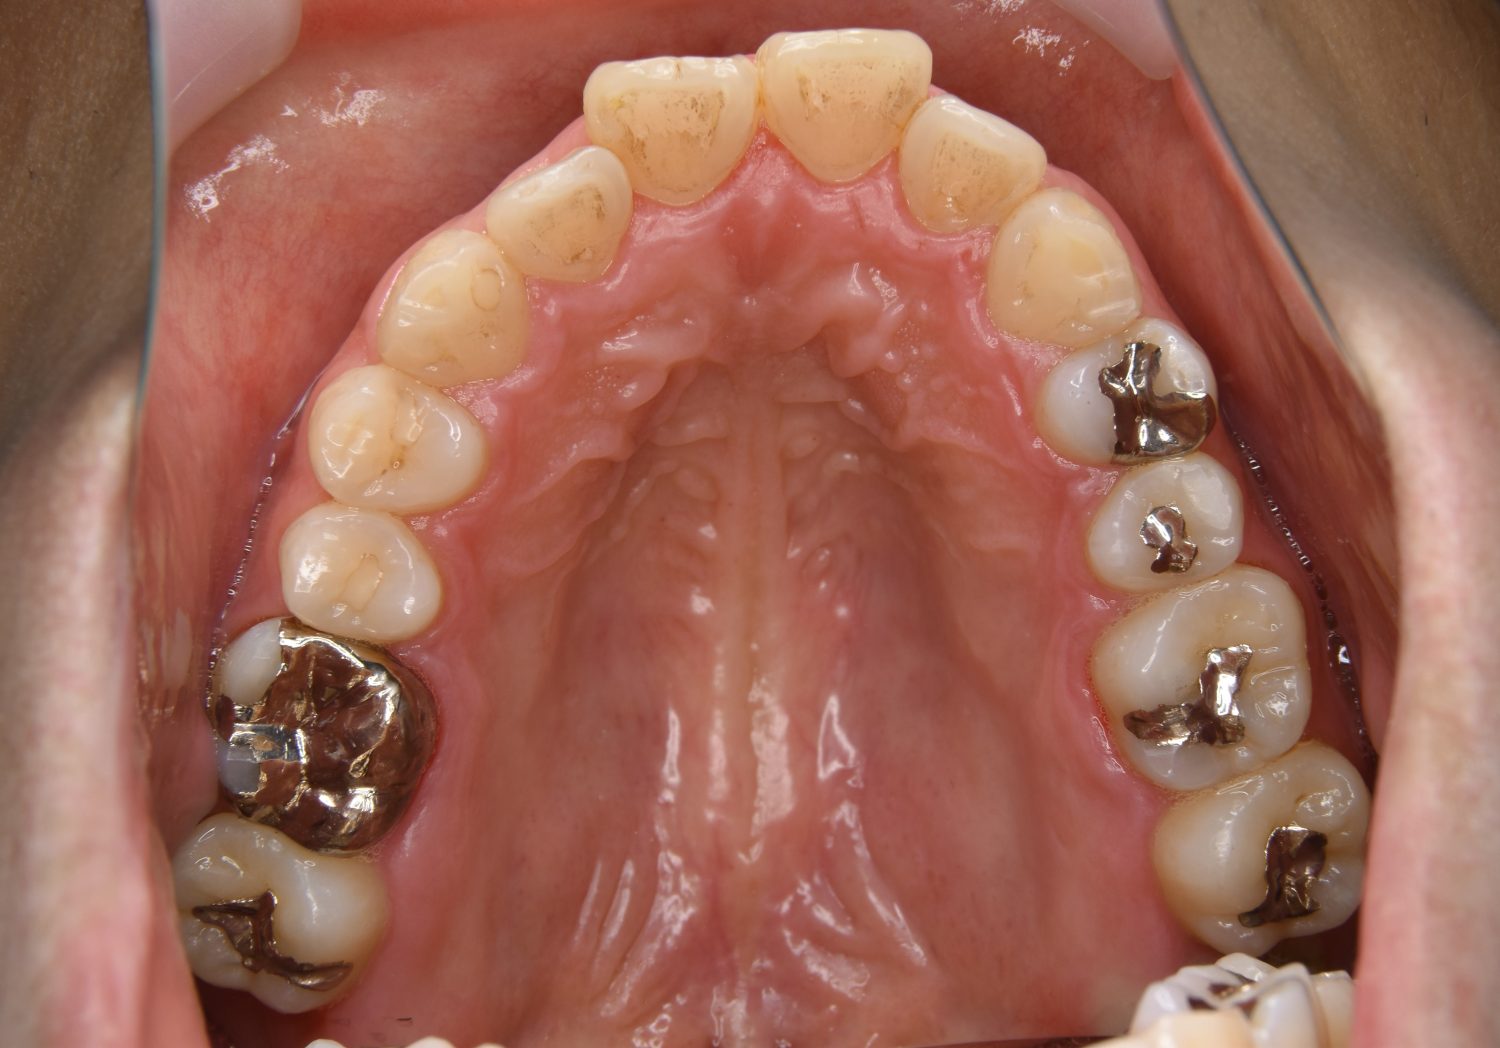

前歯部開咬の症例紹介②

Before

主訴

前歯で物が噛めない

治療内容

上下ラビアルブラケット(唇側装置)に矯正用アンカースクリューを併用し非抜歯で治療を行いました。

治療費

1,000,000 円(税込)

治療期間

26ヶ月

通院回数

27回

想定されたリスク

※歯根吸収、歯肉退縮、歯髄壊死、顎関節症状

上下の前歯が開いており前歯では全く噛めていない状態でした。臼歯の圧下を行うことで機能面のみでなく審美面も改善しました。